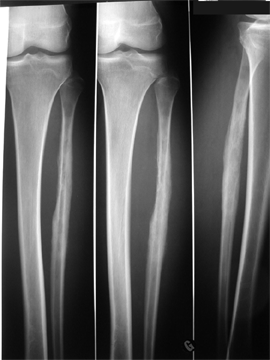

Les pathologies tumorales localisées :

Bénignes :

Ostéome ostéoïde, dysplasie fibreuse,…